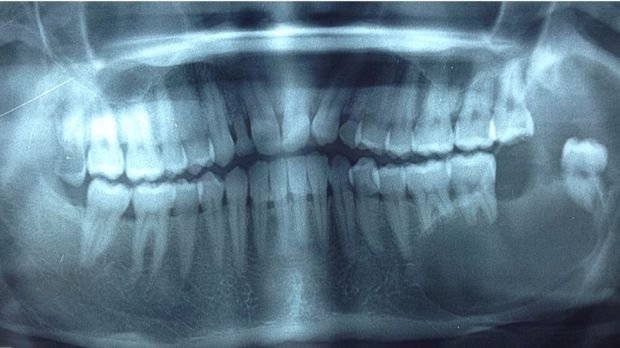

Tulang rahang yang menggelembung dan berlubang karena terkena tekanan kistik (Foto: drg Dhanni Gustiana SpBMM) |

Tulang rahang yang menggelembung dan berlubang karena terkena tekanan kistik (Foto: drg Dhanni Gustiana SpBMM)